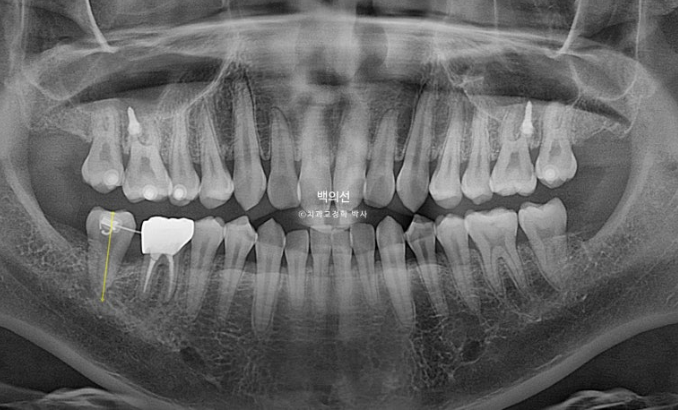

특히 아래 두번째 큰어금니는 쓰러져 있습니다.

노란선이 쓰러져 있는 큰어금니죠. 사랑니를 빼고 세워야 합니다.

문제의 쓰러진 큰어금니는 앞의 큰어금니에 걸려있는 상태로, 인비절라인 투명교정장치 만으로 세우기는 힘들어요.

클리피씨와 같은 브라켓을 붙이고 철사의 힘을 빌려야 합니다.